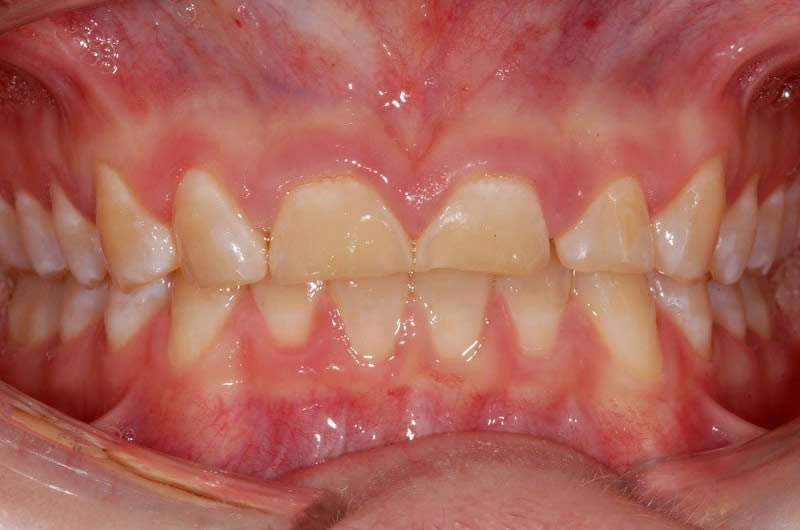

Case Studies

Upper crowns and lower composites (4 images)